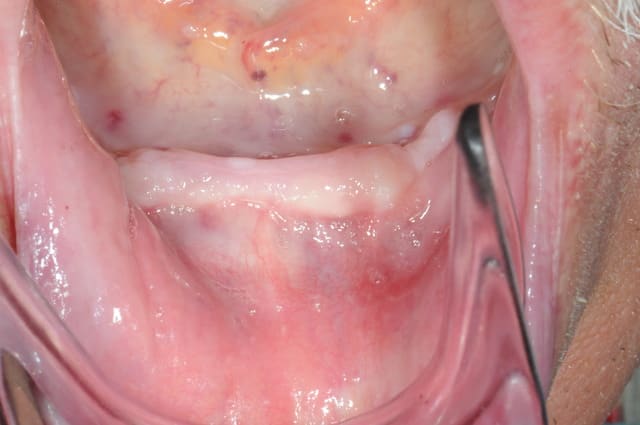

Bon, je viens de lui poser ses 4 mini-implants ce matin.(diamètre2.8 longueur 13mm)

je crois que comme ils ne sont pas trop mal disposées, je vais les solidariser par une barre d'Ackerman plutôt que 4 boules.

la photo 8 donne l'impression d'un axe en direction linguale certainement trompeuse.

non, c'était juste pour la photo et montrer qu'on pouvait poser à la main (dure dure), au CA et avec la clé...